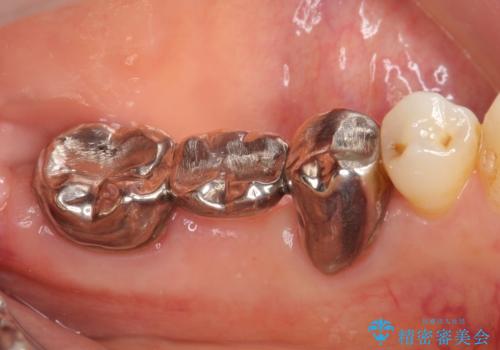

- 他院にて左下奥歯のポケットが深いと言われた、銀歯と歯茎の隙間も気になるのでまとめて治療して欲しいと来院された方の症例です。

左下7の遠心部は部分的な骨欠損によるポケットが10mmあったため、再生療法による骨の再生を行いました。